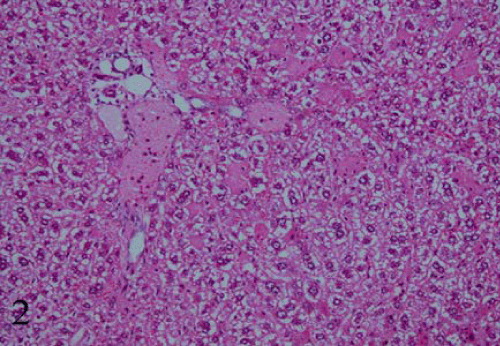

| Figure 2: A section in the liver drenched Commercial pear drink at dose (0.8 mg/kg b.w./day) for 3week showing vacuolar degeneration and hepatocellular necrosis associated with edematous which surrounded by aggregation of inflammatory cells, proliferation and dilation of bile duct, signs of fibrosis could be seen (Hx&E x200). |